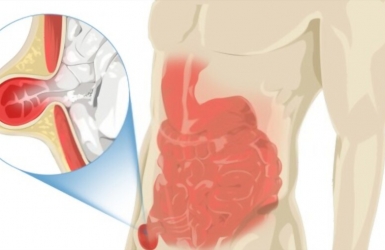

Phẫu thuật nội soi hoàn toàn ngoài phúc mạc (TEP) điều trị thoát vị bẹn

Mới đây, Bệnh viện Đa khoa Phương Chi đã tiếp nhận một trường hợp bệnh nhân nữ, 21 tuổi, có khối phồng vùng bẹn phải. Bệnh nhân khai từ nhỏ, thỉnh thoảng có khối phồng lên ở vùng bẹn phải, thường xuất hiện khi đứng lâu hay làm việc nặng. Gần đây tần suất tăng lên, gây đau.

Tìm hiểu về phẫu thuật nội soi điều trị thoát vị bẹn

Phẫu thuật nội soi điều trị thoát vị bẹn ngày càng phổ biến với nhiều ưu điểm: ít đau sau mổ, vết mổ thẩm mỹ, thời gian trở lại sinh hoạt ngắn.

Thoát vị bẹn: Triệu chứng và cách điều trị

Thoát vị bẹn là bệnh lý rất thường gặp đặc biệt ở nam giới. Phẫu thuật là phương pháp điều trị tốt nhất. Ở Bệnh viện đa khoa Phương Chi có thể thực hiện nhiều kỹ thuật điều trị bệnh lý này (mổ hở, nội soi). Khi thấy có khối phồng bất thường vùng bẹn, bìu thì nên đến bệnh viện thăm khám để được chẩn đoán và điều trị kịp thời, tránh để biến chứng.